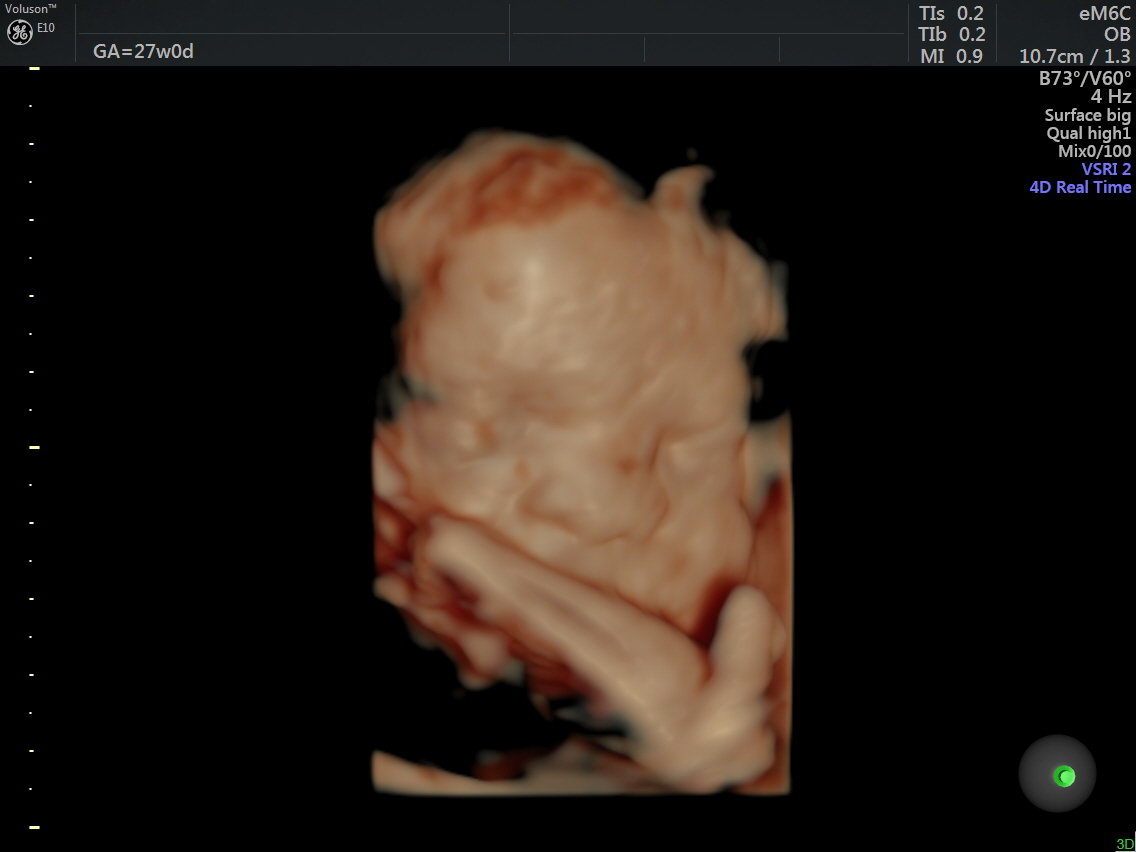

RT AORTIC ARCH_2 Published June 17, 2016 at 1136 × 852 in Rt aortic arch and aberrant left subclavian artery Next →